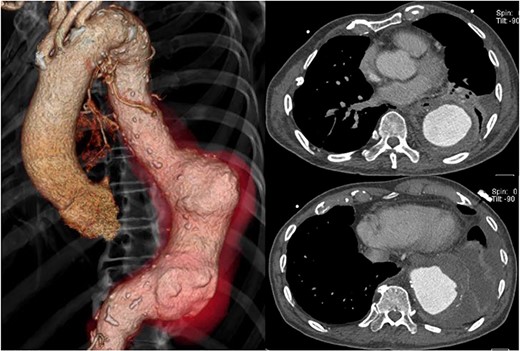

CT 15 months after reconstruction showed regression of the aneurysm, measuring 53 × 53 mm (Fig. 3). He had no further signs of infection.

CT 15 months later shows regression of the aneurysm to 53 mm in diameter.